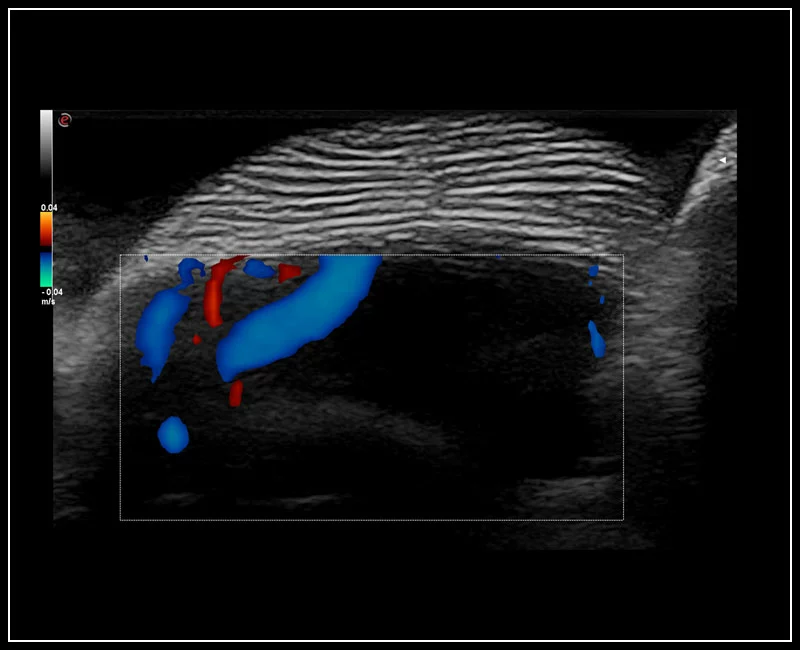

MyLab™9 Platform - Ultra-sensitivity Colour Doppler for precise visualization pulmonary veins

MyLab™9 Platform - Ultra-sensitivity Colour Doppler for precise visualization pulmonary veins